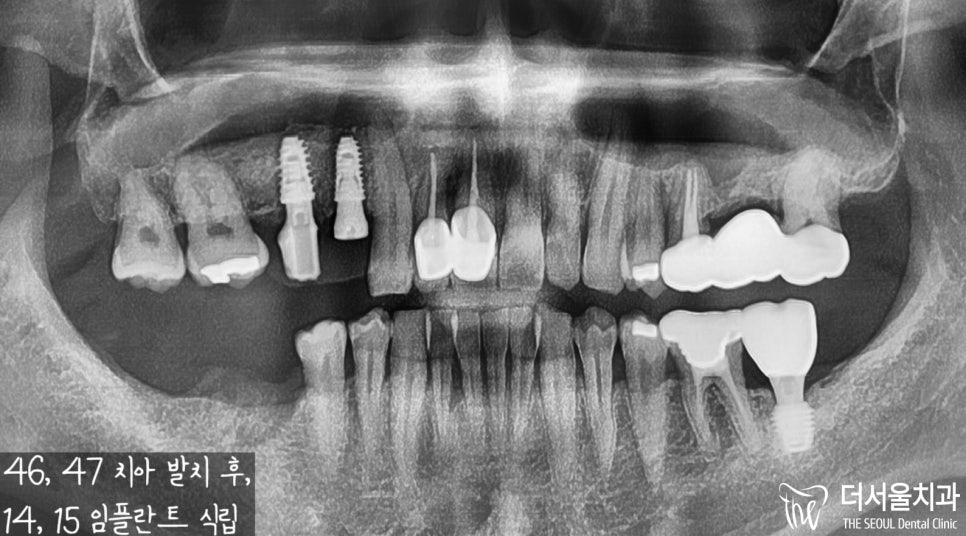

# 46, 47 뿌리 쪽으로

잇몸 염증이 발생했습니다.

골소실이 나타난 것도 볼 수 있었고,

# 46 치아는 조금 쓰러짐이 발생한 것을

확인할 수 있었습니다.

결국 판교역 치과 의료진이 내린 진단은

발거 후 임플란트 식립이었습니다.

잇몸 염증 및 골소실이 진행되고 있었기에

달리 치료로 해결할 방법이 없었습니다.

위에 # 14, 15번 자리에

픽스처와 지대주를 세팅했습니다.

골유착이 이뤄지기를 기다릴때,

크라운 제작에 들어갔구요.

그 다음은 오른쪽 아래 어금니

임플란트 식립 계획을

컴퓨터 분석 프로그램으로

수립 과정을 거쳤습니다.

신경관과 거리는 가깝지 않은지,

뼈 두께나 깊이는 얼마나 되며

어떤 직경의 픽스처를 심어드리면 되는지,

그 외에 조심해야될 사항은 없을지

꼼꼼히 체크한 뒤에 수술을 진행했습니다.